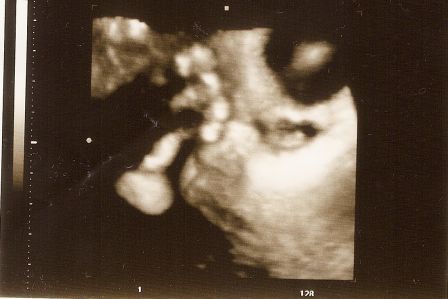

szerintem nem baj, ha ismét kisebbnek mérték egy héttel, hihetetlen, hogy már 35 hetes!